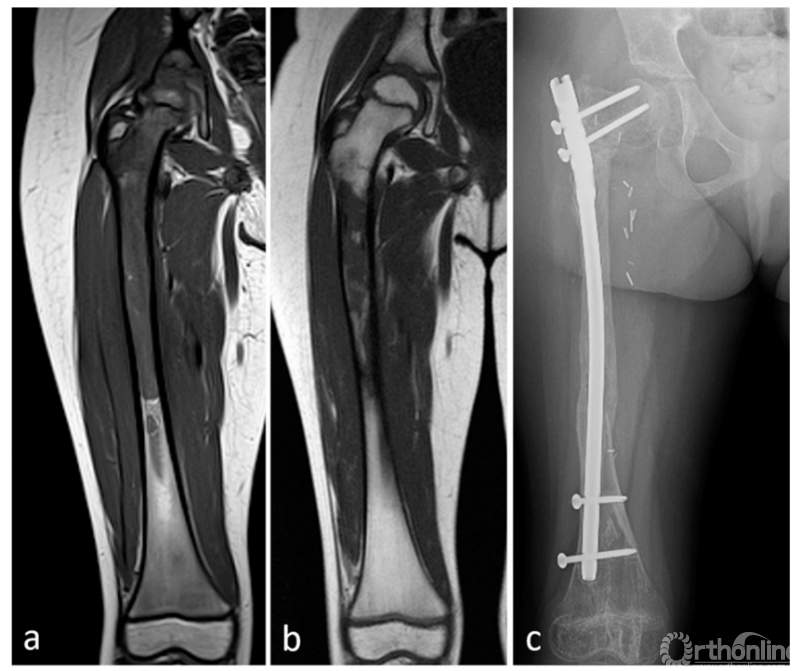

由放射科医生以标准化方式对化疗前、后的MRI进行分析。研究纳入了三个MRI序列:T1加权、T1增强以及STIR序列。对于每个序列,通过冠状面上的异常信号和正常信号来确定肿瘤的范围。测量骨内异常信号的近端和远端边界与相应的骨末端之间的距离(图1A和1B)。

图1 8岁男孩左胫骨尤文氏肉瘤。图1A,化疗前T1加权。表示骨近端到肿瘤近端界限的距离(x)和骨远端到肿瘤远端界限的距离(x’);图1B,化疗后T1加权。表示骨近端到肿瘤近端界限的距离(y)和骨远端到肿瘤远端界限的距离(y’);图1C,显示组织学测量。在本例中,近端(z)和远端(z’)测量值表示各自肿瘤极限与手术标本上切割的骨之间的距离,加上计算机X光片上测量的残骨长度。

在切除的标本上,测量了肿瘤边界(近端和远端)与相应骨末端之间的距离。当末端包括骨骺时,这种组织学测量就足够了。当末端是骨切面时,在组织学测量中添加了术后X线检查中测量的骨切面与残余骨末端之间的距离。这2个距离的总和对应于肿瘤相对于骨末端的距离(图1C)。